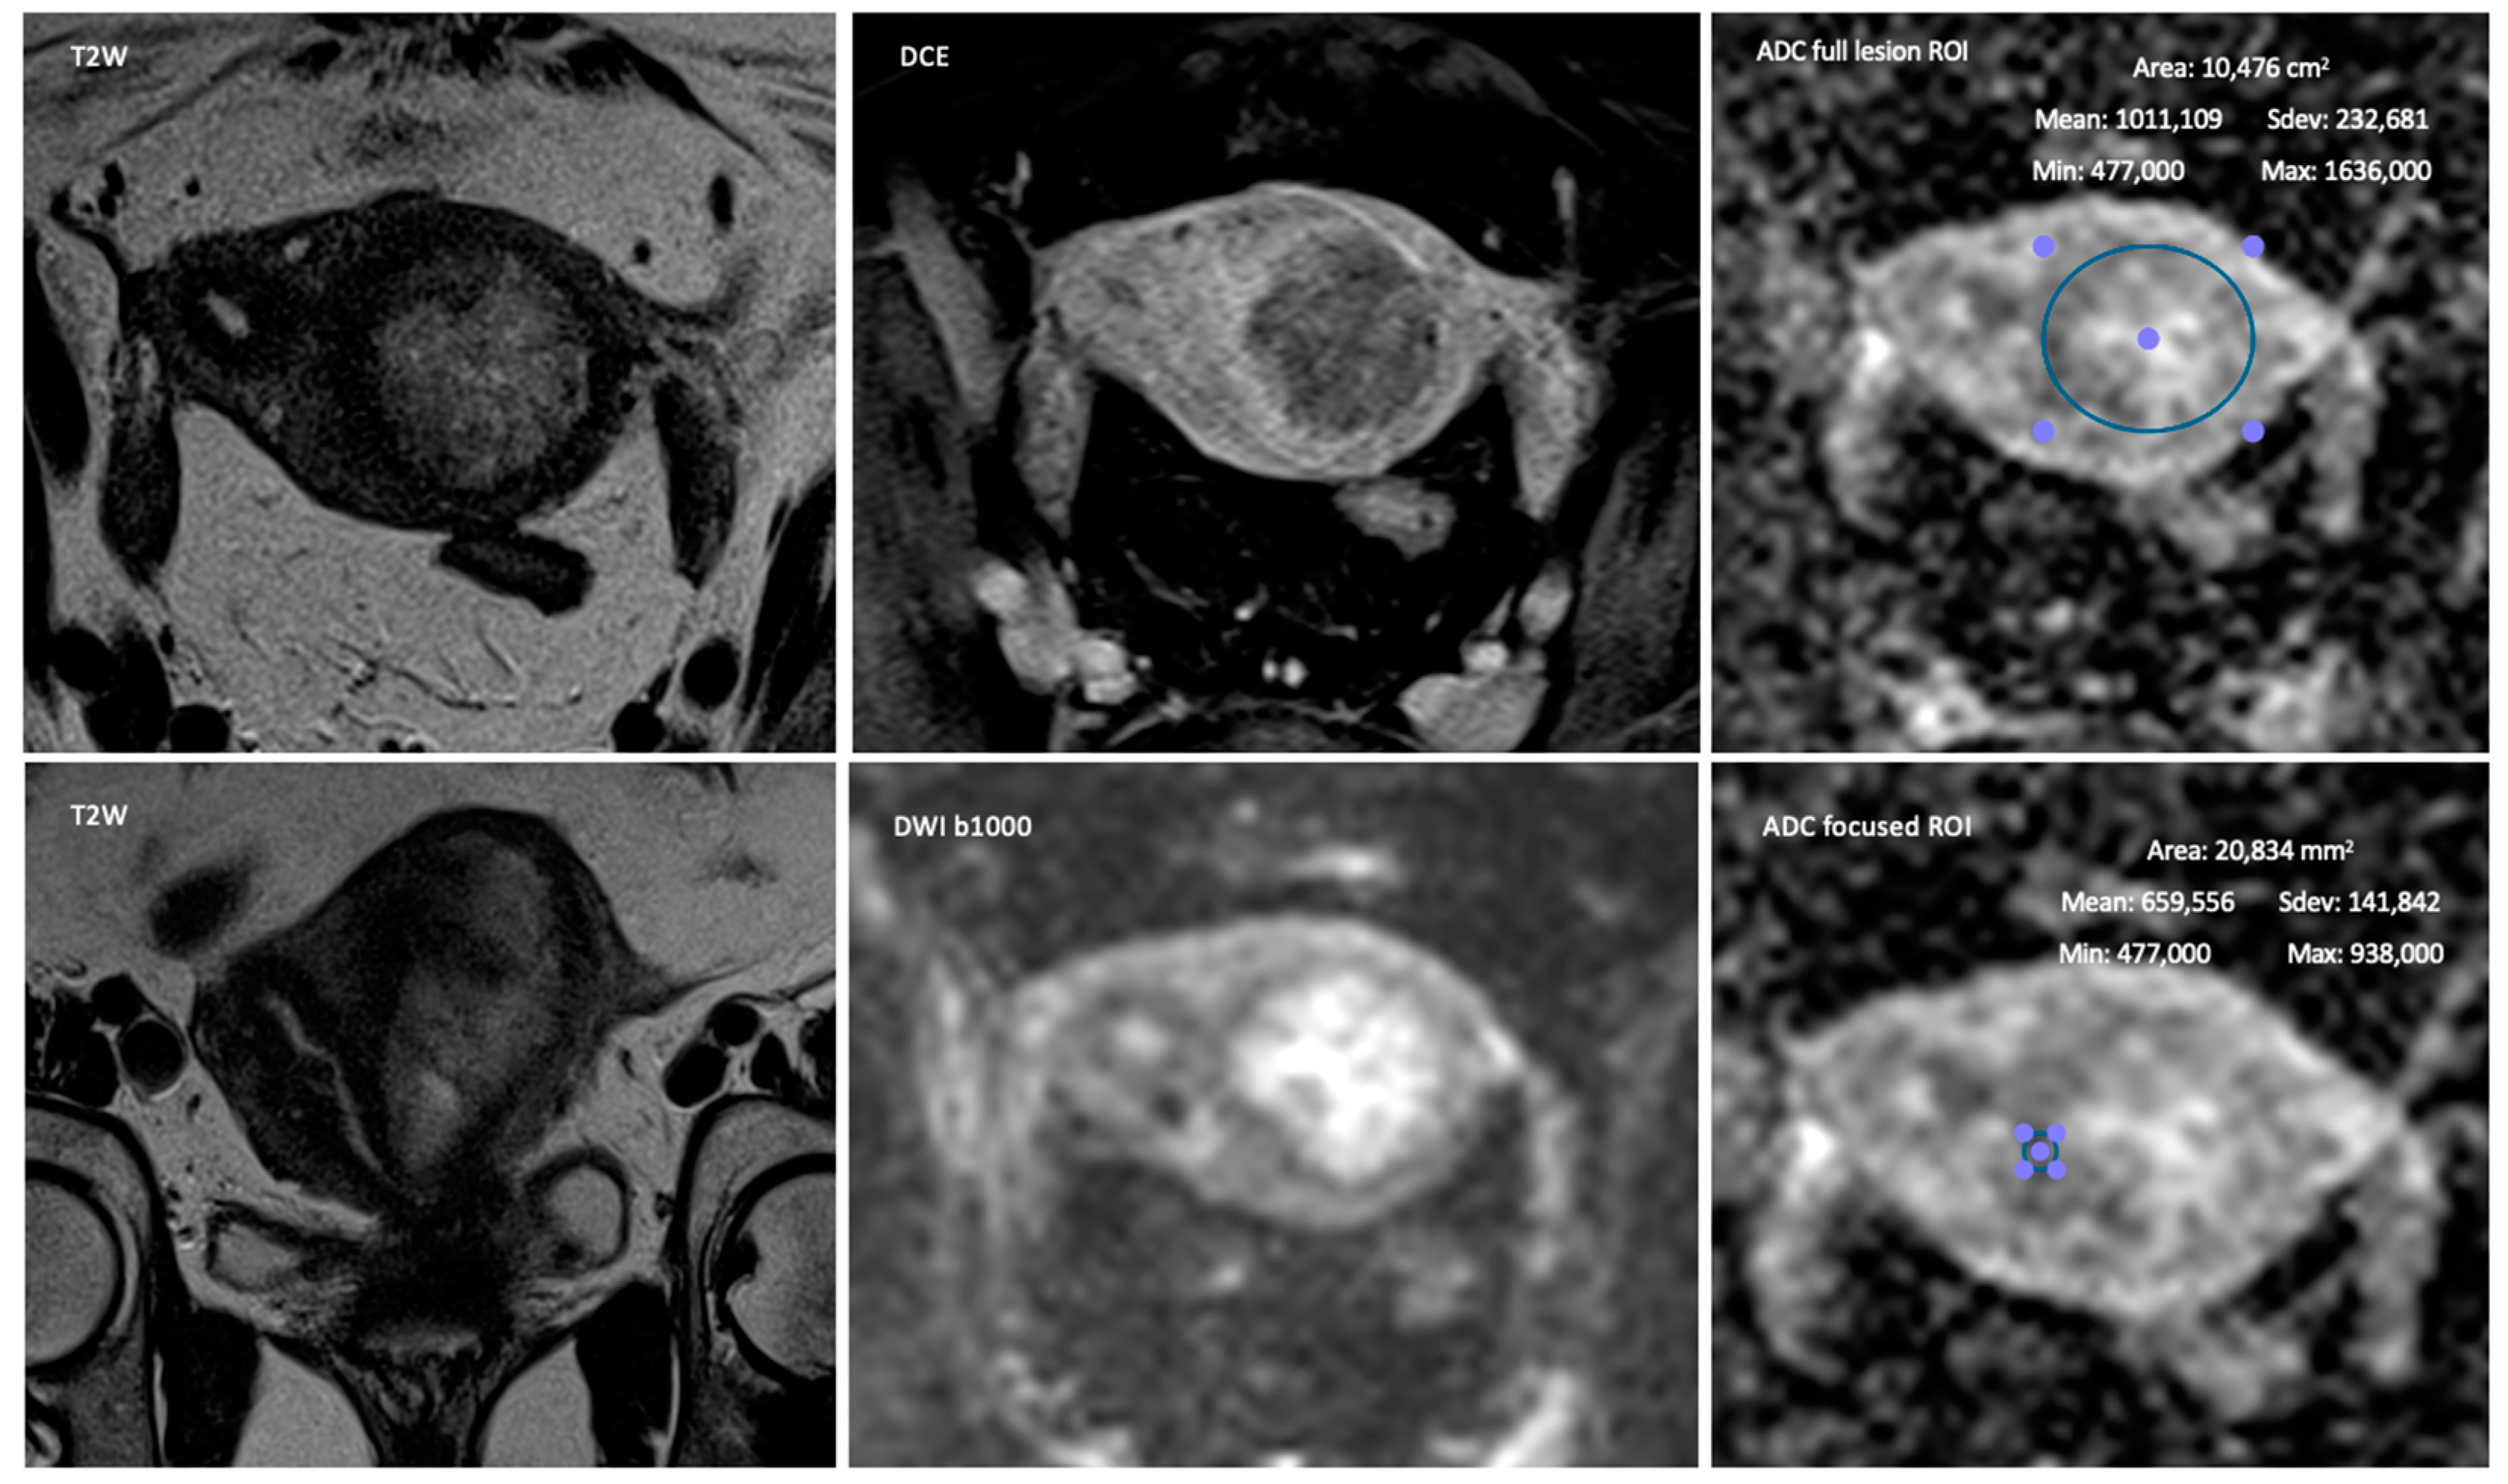

2.2. MR Imaging

2.3. Image Interpretation